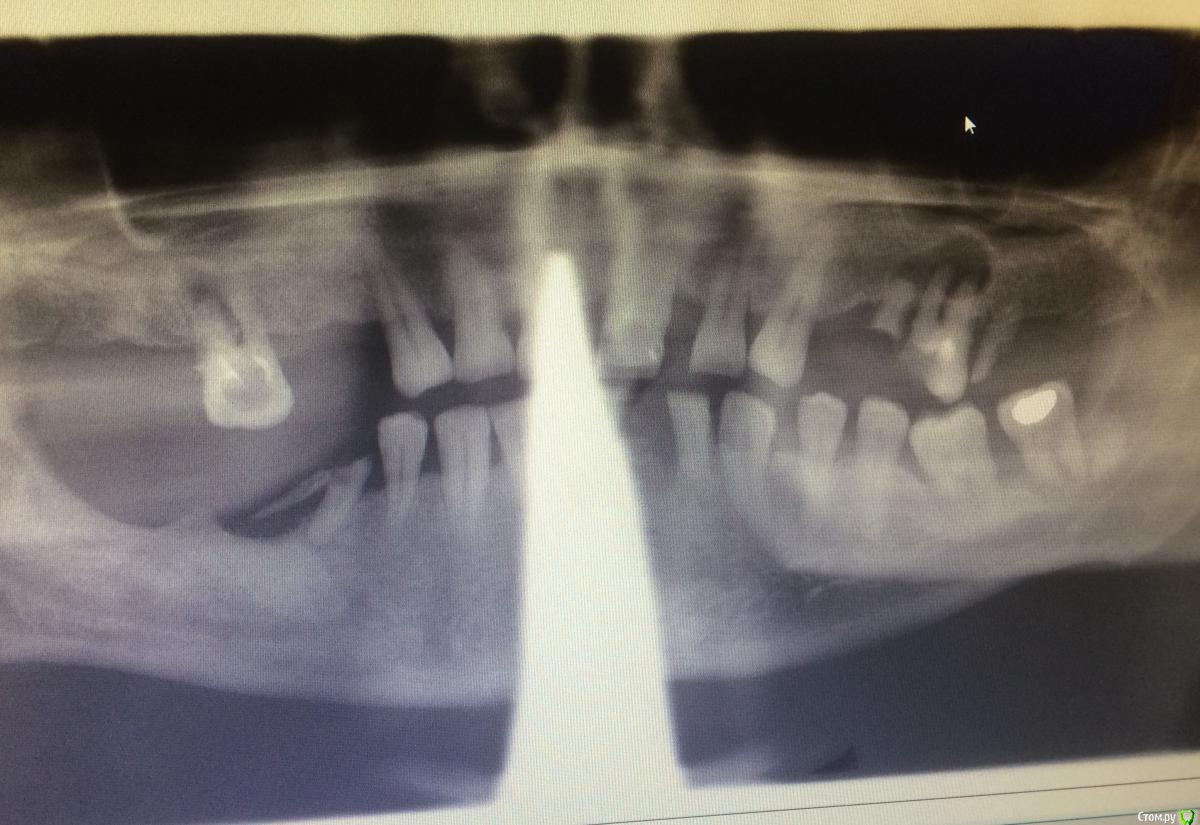

Larnary Опубликовано 25 января, 2015 Поделиться Опубликовано 25 января, 2015 Добрый вечер! Надо санировать и спротезировать близкого человека. Хотел бы посоветоваться.жевательные зубы нижней челюсти будут восстанавливаться имплантами. Нужно ли поднимать высоту гребня? 36,37 думаю удалять. Если да,то каким способом это лучше и проще сделать? Во фронтальном участке уже удалены 32,31,41. Фронт с 35 по 44 планируется мост диоксид циркония. И второе, будет ли верным удалить верхние моляры с подсыпкой коллапаном(био осс сейчас нет возможности купить,а коллапана в клинике море)а через 5-6мес восстановить имплантами? Прошу прощения за поганый снимок,но какой есть.после удаления необходимых зубов уже потребую качественный Ссылка на комментарий

колесников Опубликовано 26 января, 2015 Поделиться Опубликовано 26 января, 2015 (изменено) здравствуйте! не торопитесь городить мосты и крутить винты. если это свой,то не поленитесь поискать для него хорошего ортодонта.( удалять кстати тоже поторопились. подвижные двойки-единицы надо было вытянуть ортодонтически,а то кости и так мало). однозначно временное съёмное протезирование. верхние моляры удалить. подсыпать или нет и что подспать-решать вам. но только не колапан. возьмите остеопласт к (спасибо тов иванову). порядка 2500 за 2грамма. вот 36,37 у меня сомнения вызывают ,удалишь сразу-получишь провал нехилый .. может тоже попробовать выдвижение и отсроченое удаление? посоветуйтесь с ортодонтом. 44 не жилец. ненадо на него цирконий тратить Изменено 26 января, 2015 пользователем колесников Ссылка на комментарий

Larnary Опубликовано 26 января, 2015 Автор Поделиться Опубликовано 26 января, 2015 (изменено) 44 не жилец? Странно. Может все-таки 45 не жилец? Там рядом еще корень от 46 лежит. И еще,не уверен,что мужчина 55лет согласится на брекеты)))А вот провал кости в области 36,37 реально беспокоит Изменено 26 января, 2015 пользователем Larnary Ссылка на комментарий

колесников Опубликовано 26 января, 2015 Поделиться Опубликовано 26 января, 2015 44 не жилец? Странно. Может все-таки 45 не жилец? Там рядом еще корень от 46 лежит. И еще,не уверен,что мужчина 55лет согласится на брекеты)))А вот провал кости в области 36,37 реально беспокоитиз-за фартука мне не видно. подумал что это корень 45го прошу прощения....по поводу ортодонтии :вы ещё не прикинули план действий,не озвучили его пациенту,а уже вынесли за него решение. идеальный план всегда включает ортодонтический этап,пусть даже для хирургического пособия. вы ведь сказали что это свой пациент,хотите для него лучшего, надо настоять,рассказать,объяснить. если он хочет всё ,сразу и быстро-это не к нам. это в гос поликлинику, всё удалять и 2 чсп. хочет красиво и надолго-придётся молча согласится со специалистами. Ссылка на комментарий